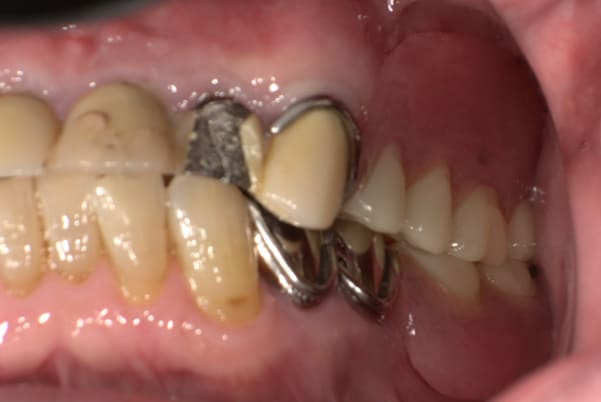

上の前歯が重度歯周病により動揺し、残せない状態のため、入れ歯も動揺がありました。

ご自身の歯に負担の少ないバネ、また見た目も改善

ご自身の歯に負担の少ないバネ

銀歯からセラミック歯に

バネをかける歯は繋げることで強度を増し、歯への負担を軽減し、歯の寿命を長くする設計へ。

バネがかかる歯の被せ物は、歯への負担を減らし、入れ歯が動きにくいようになる形態をあらかじめ付与することで、より入れ歯の機能が高まります。

治療を行う際、被せ物や入れ歯は、別々に考えるのではなく、一口腔単位としてお口全体のことを考え最良の治療計画を立てることが歯の寿命、機能効果を向上させるため、専門医としてこのことは常に心掛けて治療を行っています。

残りの歯に負担がかからないよう、被せ物と入れ歯の一体化を図った入れ歯

治療前は上下奥歯の入れ歯が削れていることで、かみ合わせが低くなり唇もつむった状態でした。

かみ合わせを適切な高さに戻したことで、本来の自然な口元へ。